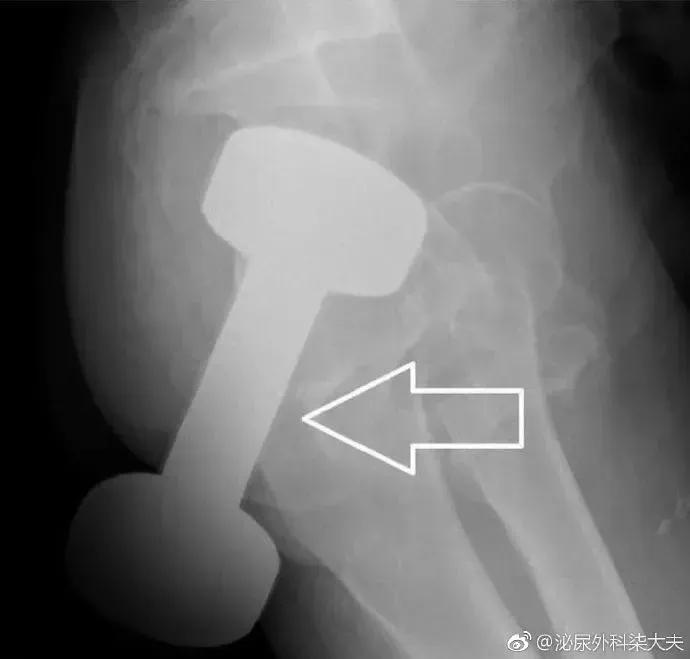

急诊来了个患者,直肠异物,平片显示是个灯泡,灯泡当然是要取出来的。但有两个要求:第一,不能把灯泡弄碎,这样可能会损伤直肠;第二,尽量不做手术,手术创伤大,如果做手术,可能要做造口。满足两个条件的前提下大家有什么好方法把灯泡完整取出?

医生会通过一系列检查如直肠指诊、X线来确定体内的异物是什么,在什么位置,这一点非常关键,因为只有搞清楚里面的真实情况,医生才能找到合适的方法把异物取出。